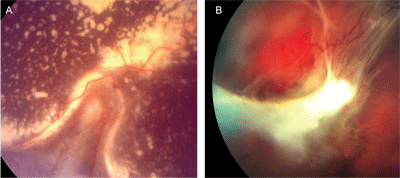

Hiện tại e đang đợi ngày XN lại nhưng vẫn rất lo lắng. E hiện tai thấy ngứa hơi hơi ở da dưới chân và mắt hơi nhột, ngứa ở vùng mắt (e có nhờ bsi xem mắt có bị giun đũa chó lên không nhưng BS nói mắt e vẫn bình thường). Vẫn lo lắng nên e đã có XN máu ở BVĐK Hoàn Mỹ Cửu Long tai Cần Thơ thi âm tính với giun đũa chó.

Về triệu chứng lâm sàng, lẽ đương nhiên đối với bệnh ấu trùng giun đũa chó mèo thường có hội chứng ở mắt (Ocular Larval migrans_OLMs), thể phủ tạng (Viceral Larval migrans_VLMs) và thể thông thường hay tiềm ẩn (Occult Toxocariasis), nên có thể triệu chứng trêm mắt như bạn đề cập có thể do ấu trùng giun đũa chó mèo hoặc một tác nhân nhiễm trùng (có thể nhìn thấy trên hình ảnh) hoặc động vật chân khớp khác như Demodex canis chẳng hạn. Nên có thể bạn nên thăm khám và xét nghiệm thêm tại một số trung tâm lớn để tìm thêm tác nhân gây bệnh khác có thể dẫn đến cho bạn ngứa như mô tả như trên.